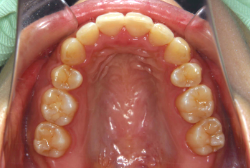

叢生(そうせい)

凸凹な歯並びのことを叢生といいます。矯正歯科に来院する患者様の主訴の中で、最も多いのが「配列の凸凹を真っ直ぐにしたい」というものです。歯の大きさと顎の大きさの調和がとれていないことが原因です。

凸凹を主体としたケースの場合、当院の平均治療期間は18ヶ月ですので、このケースは少し長めに経過しました。理由の一つは凸凹の程度がかなり重症だったと言うことですが、もう一つは、右下第2大臼歯が45度くらい前傾していたため、それを整直化させるために時間を要したと考えています。いずれにしても最終結果は大変よい状態と思います。

治療前は並びが乱れて見た目が悪いというのはもちろん問題ですが、歯科医学的に一番困るのは噛み合わせが悪いという点です。上下の犬歯(3番目の歯)は、上下的に離れた位置にあるため接触することができません。つまり歯としては存在していても、歯としては機能していないということです。